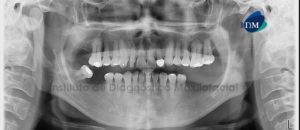

Paciente de 51 años de edad acude al Instituto de Diagnóstico Maxilofacial (IDM) para su evaluación general. A la evaluación de la radiografía panorámica se aprecia